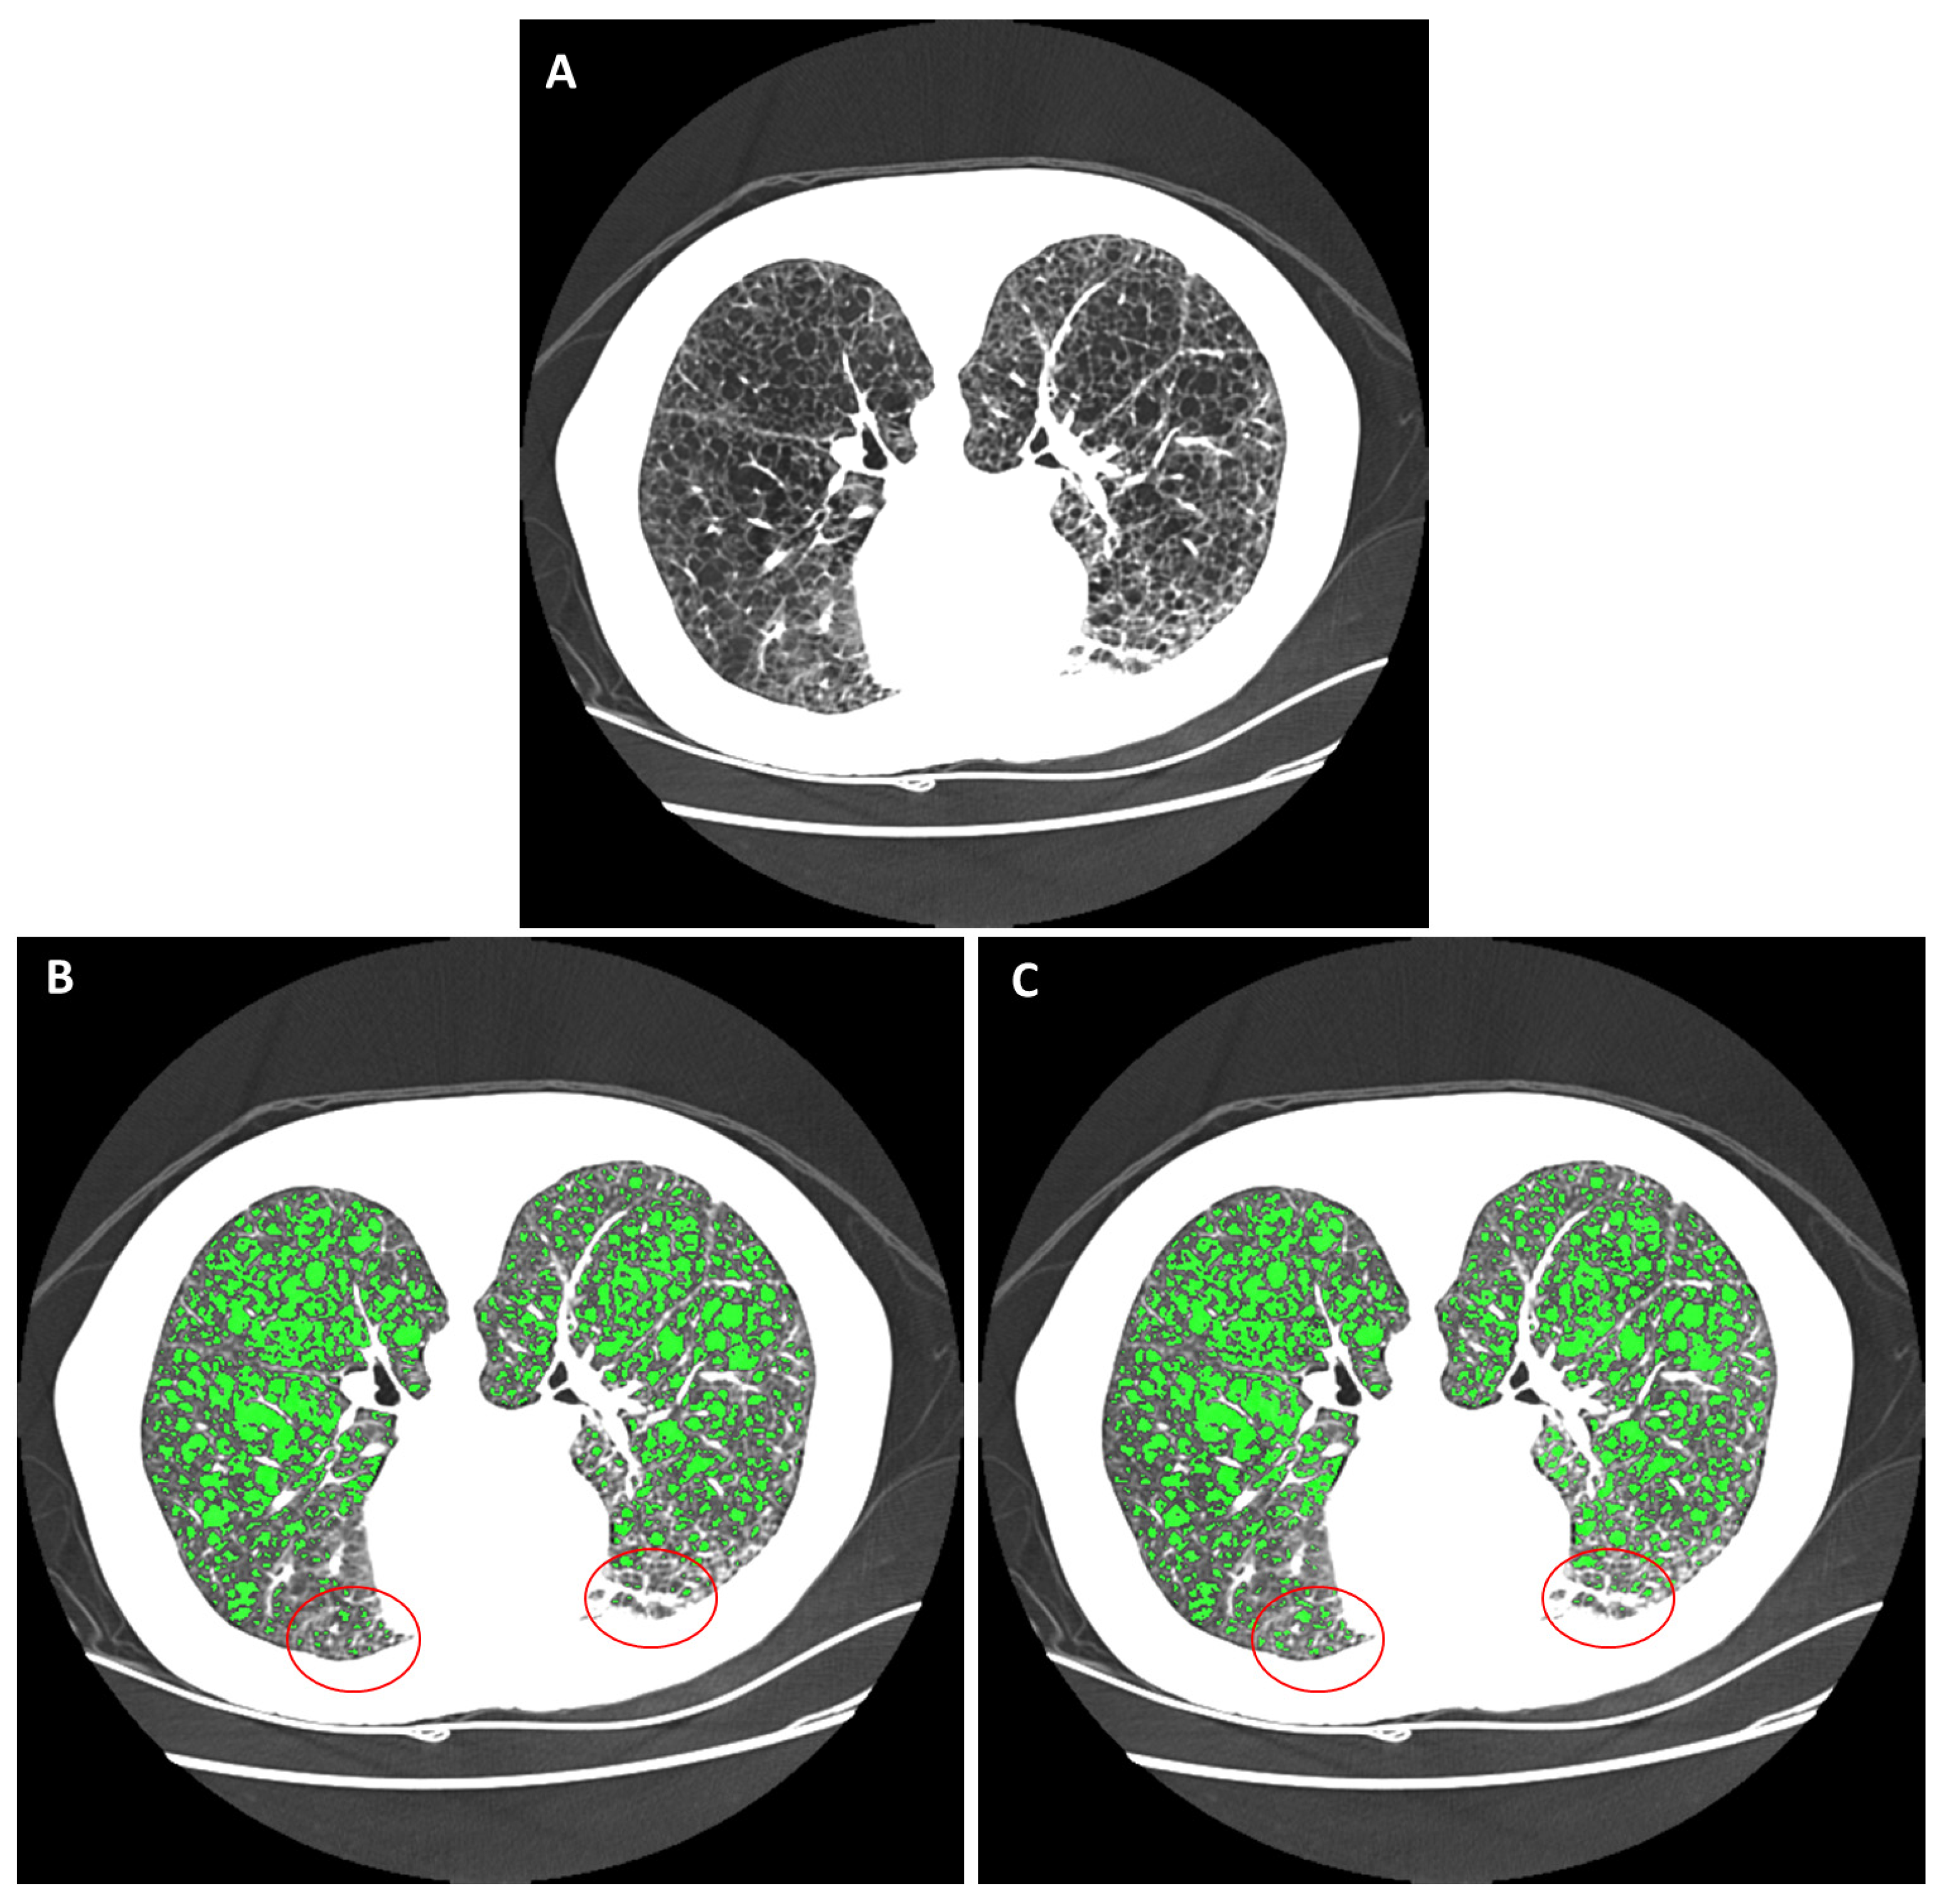

Figure 5.

An example of within-section variability of the radiodensity of the pulmonary parenchyma and its impact on cyst segmentation. (A) An HRCT section of a LAM patient lying in the prone orientation is displayed in the grayscale range of −1100 HU to −500 HU. The anterior portion of the lungs was enhanced due to positional atelectasis. (B) The gold-standard semi-automated segmentation by a trained operator, who set a global threshold for cystic areas to −930 HU. Cystic areas are highlighted in green. The anterior region of the lungs was under-segmented due to the elevated parenchymal radiodensity there (highlighted by the red circles). (C) The automated cyst segmentation. The automated method accounted for regional variations of radiodensity, which mitigated the problem of under-segmentation in the anterior region.

An example of cyst segmentation in the presence of variable parenchymal radiodensity within the same section is given in Figure 5. In this example, the anterior portion of the chest was enhanced by positional atelectasis (Figure 5A). The reference standard semi-automated segmentation was optimized by the operator at a global threshold of −930 HU for cysts (Figure 5B). However, the anterior portion (outlined in red in Figure 5B) was under-segmented. This was mitigated by the automated segmentation (Figure 5C).